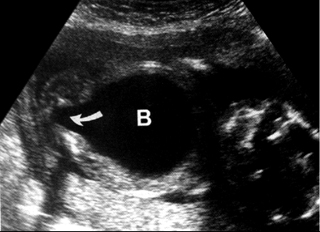

Οι ουρητηροκήλες απεικονίζονται ως μια μικρή κυκλική περιοχή μέσα στην ουροδόχο

κύστη, με λεπτό τοίχωμα και ορώδες περιεχόμενο και ανευρίσκονται συνήθως με

διπλό σύστημα νεφρού στη σύστοιχη πλευρά (εικόνες 14, 15).

| Εικόνα 13. Μεγαουρητήρας. | Εικόνα 14. Β: ουροδόχος κύστη. U: ουρητηροκήλη. | Εικόνα 15. Διπλό σύστημα νεφρού. |